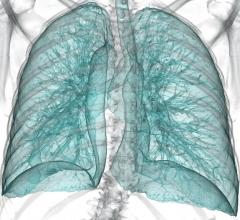

Data regarding screening of individuals at high risk for lung cancer with low-dose computed tomography (CT) presented at the 2014 Annual Meeting of the American Society of Clinical Oncology (ASCO) overestimates the costs and number of false positive exams due to its reliance on an outdated 4 mm size threshold for defining a positive screen.

The American College of Radiology (ACR) is accepting applications for its new ACR Lung Cancer Screening Center program, which recognizes facilities committed to providing quality screening care to patients at the highest risk for lung cancer.

The American College of Radiology said it is deeply disappointed at the failure of the Medicare Evidence Development & Coverage Advisory Committee (MEDCAC) to vote in support of national Medicare coverage of low-dose computed tomography (LDCT) screening for patients at high risk for lung cancer.